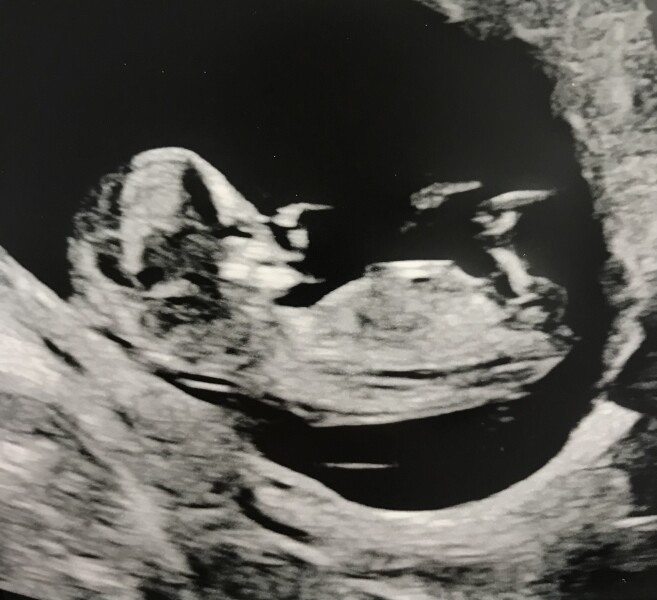

Laughingmole · 23/05/2022 17:10

My scan picture wouldn’t attach earlier but here is my bouncing bean! I’m now due 4th December.

@LolaJ87 glad yours went well too! Good luck to everyone else having their scans soon!

@Laughingmole congratulations! What a great scan. Any suspicions on the gender? Are you planning on finding out?

Congratulations @Laughingmole! What a great picture - we have the same due date!